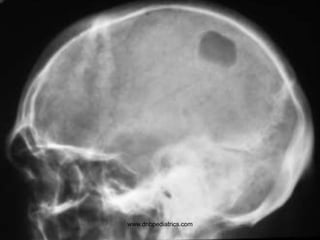

www.dnbpediatrics.com

Questions

• Describe the lesion?

• Give two D/D

• Osteolytic lesion of skull

• Histiocytosis

Metastasis

• Hyperuricemia, hyperkalemia, and

hyperphosphatemia

• Give atleast two D/D